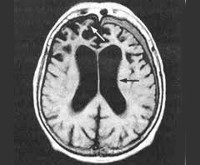

F02.4 Деменция при болезни, вызванной вирусом иммунодефицита человека [ВИЧ] (B22.0+)